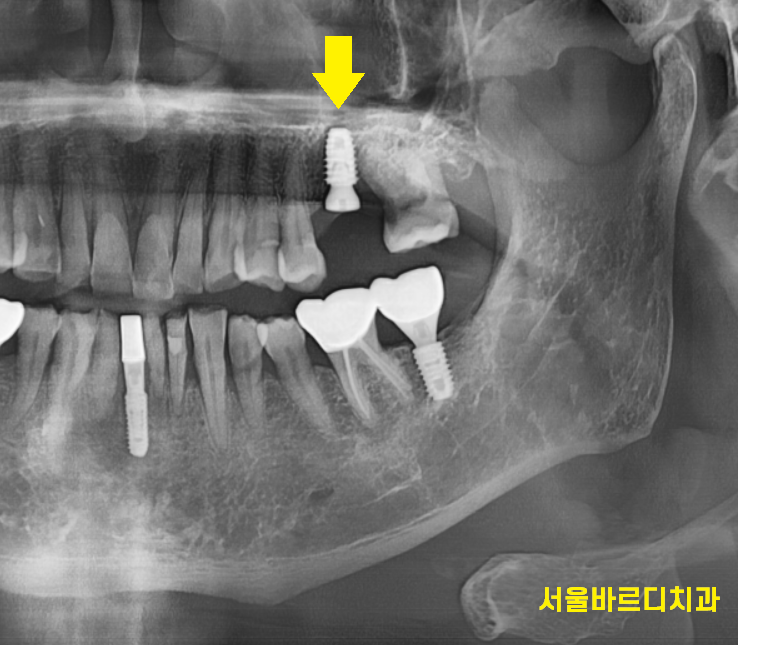

임플란트 시술은 치과에서 가장 큰 치료중 하나입니다.

치아가 상실했을 때 대체하는 치료입니다.

치아 뿌리에 해당하는 부분인데요

임플란트도 잇몸 안쪽 뼈에 식립을 한답니다.

때문에 뼈가 충분할 수록

임플란트 수술과 예후에 좋아요~

뼈가 부족한 부분에 대해서는

추가적으로 이식을 해서 보충을 해주기도 하고요.